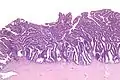

| Micrograph of a villoglandular adenocarcinoma the cervix. H&E stain. | |

The name of the lesion describes it microscopic appearance. It has nipple-like structures with fibrovascular cores (papillae) that are long in relation to their width (villus-like), which are covered with a glandular pseudostratified columnar epithelium.